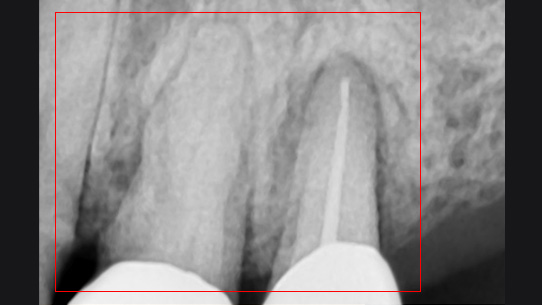

치아 뿌리 주변 염증과 치조골이 녹아내려 통증과 더불어 치아가 흔들리는 상태로 내원한 환자입니다. 우선 큐렛으로 잇몸 속 치석을 제거하였습니다. 뿌리 주변 염증은 신경관을 소독하고 약재를 삽입하는 신경치료를 시행하였습니다.

신경관 소독

신경관 약재삽입

약재주입 후 반응